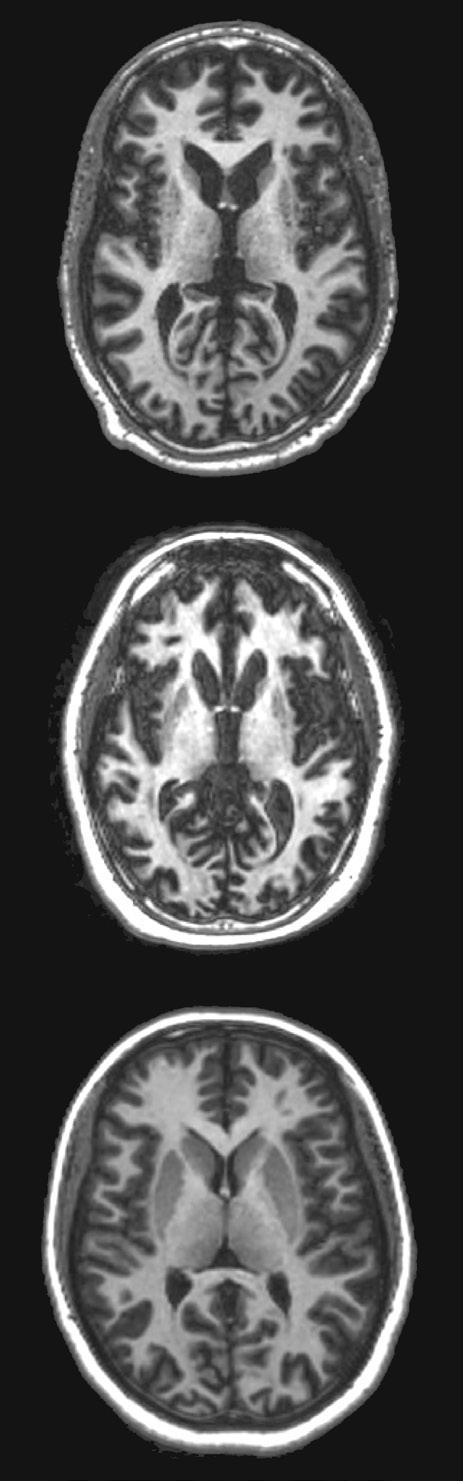

CT scans that display the presence of Huntington’s disease in the brain.

A series of CT scans that display the presence of Huntington’s disease in the brain

and intensify as time goes on. Early symptoms can be personality changes, confusion and memory loss or chorea (involuntary twitches or muscle spasms). Chorea comes from the Greek word to dance as the movements can be unexpectedly big. These regions are responsible for cognitive functions, learning and motor skills, the execution of movement as well as our memory and emotions.

AMT-130 is the new gene therapy that has been designed to slow the progression of HD. The treatment was developed by uniQure, a company specialising in gene therapies for severe and rare genetic diseases. This therapy is injected into the putamen and caudate nucleus, deep in the centre of the brain, with the aid of magnetic resonance imaging (MRI). This operation takes up to ten hours as the surgeons carefully deliver AMT-130 three separate times.

The results of UniQure’s trial showed that after around three years, there was an average 75% slowing of the disease progression. This data was collected via MRI scans and studies of the protein levels in the fluid around the brain. It shows that AMT-130 stops brain neurons from dying. However, these results do not have longer term outcomes; positive or negative. It could be that AMT-130 solves more problems than we thought, or it could create unforeseeable problems down the line.